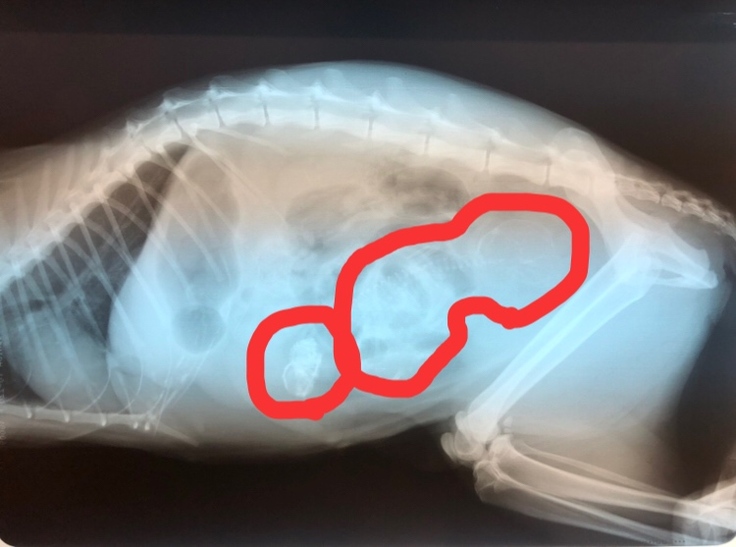

そして、レントゲン写真を見せて

頂き、お腹の中の赤ちゃん。

左の小さい子は大きくなれなかった

そうです。。

そして、右の赤ちゃん。

6日現在(昨日)もまだ生きています!!

先生も、膜も出てきてるのに……と。

凄い生命力です……。。